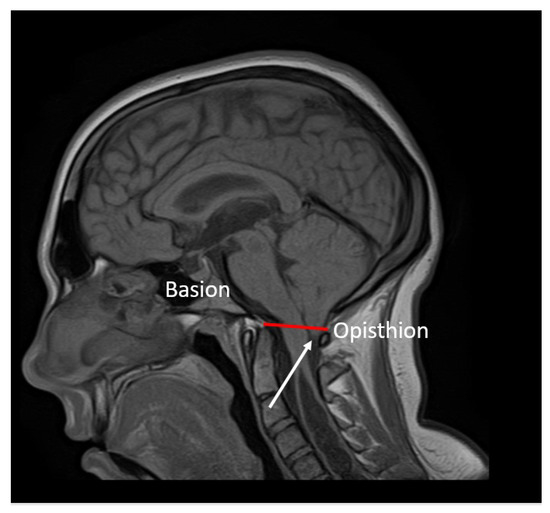

Chiari 1 Malformation (CM1) is classically defined as a caudal displacement of the cerebellar tonsils through the foramen magnum into the spinal cord. Modern imaging techniques and experimental studies disclose a different etiology for the development of CM1, but the main etiology factor [...] Read more.

Chiari 1 Malformation (CM1) is classically defined as a caudal displacement of the cerebellar tonsils through the foramen magnum into the spinal cord. Modern imaging techniques and experimental studies disclose a different etiology for the development of CM1, but the main etiology factor is a structural defect in the skull as a deformity or partial reduction, which push down the lower part of the brain and cause the cerebellum to compress into the spinal canal. CM1 is classified as a rare disease. CM1 can present with a wide variety of symptoms, also non-specific, with consequent controversies on diagnosis and surgical decision-making, particularly in asymptomatic or minimally symptomatic. Other disorders, such as syringomyelia (Syr), hydrocephalus, and craniocervical instability can be associated at the time of the diagnosis or appear secondarily. Therefore, CM1-related Syr is defined as a single or multiple fluid-filled cavities within the spinal cord and/or the bulb. A rare CM1-related disorder is syndrome of lateral amyotrophic sclerosis (ALS mimic syndrome). We present a unique clinical case of ALS mimic syndrome in a young man with CM1 and a huge singular syringomyelic cyst with a length from segment C2 to Th12. At the same time, the clinical picture showed upper hypotonic-atrophic paraparesis in the absence of motor disorders in the lower extremities. Interestingly, this patient did not have a disorder of superficial and deep types of sensitivity. This made it difficult to diagnose CM1. For a long time, the patient’s symptoms were regarded as a manifestation of ALS, as an independent neurological disease, and not as a related disorder of CM1. Surgical treatment for CM1 was not effective, but it allowed to stabilize the course of CM1-related ALS mimic syndrome over the next two years. Full article